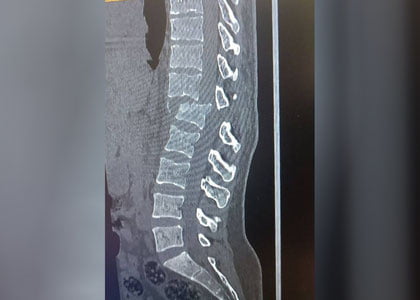

Sud qaroridan keyin erkak turmush o‘rtog‘iga tahdidli xabarlar yuborib, aliment to‘lovlarini to‘xtatishni talab qilgan. 14-avgust kuni ertalab u ayolini yo‘l chetida ketayotgan vaqtida avtomobil bilan urib yuborgan. Ayol umurtqa pog‘onasidan jarohat olib, falaj holatga tushgan va hozirda og‘ir ahvolda shifoxonada davolanmoqda.